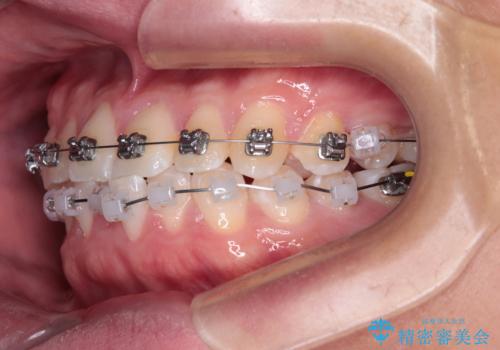

・費用と期間を抑えるために、多少目立っても効率の良いメタルブラケットを使用

・奥歯のシザーズバイト改善には、口蓋側にアンカースクリュー(TAD)を設置し、矯正用ゴムで内側に牽引

・捻転した第二小臼歯は、ワイヤーと矯正用ゴムの力を用いて正しい位置へ回転移動